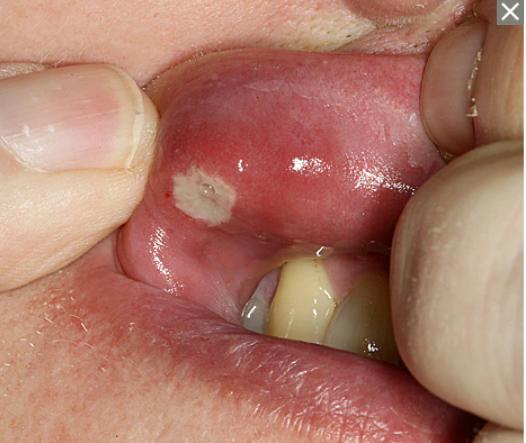

它也称为口疮性溃疡,是一种小而浅的病变,发生在口腔软组织或牙龈底部。 与唇疱疹不同,口腔溃疡不会出现在嘴唇表面,也不会传染。 大多数口腔溃疡会在一两周内自行消失。(图片像不像我们对着镜子看溃疡的样子,好痛好痛呀![大哭])

图片来源:梅奥诊所